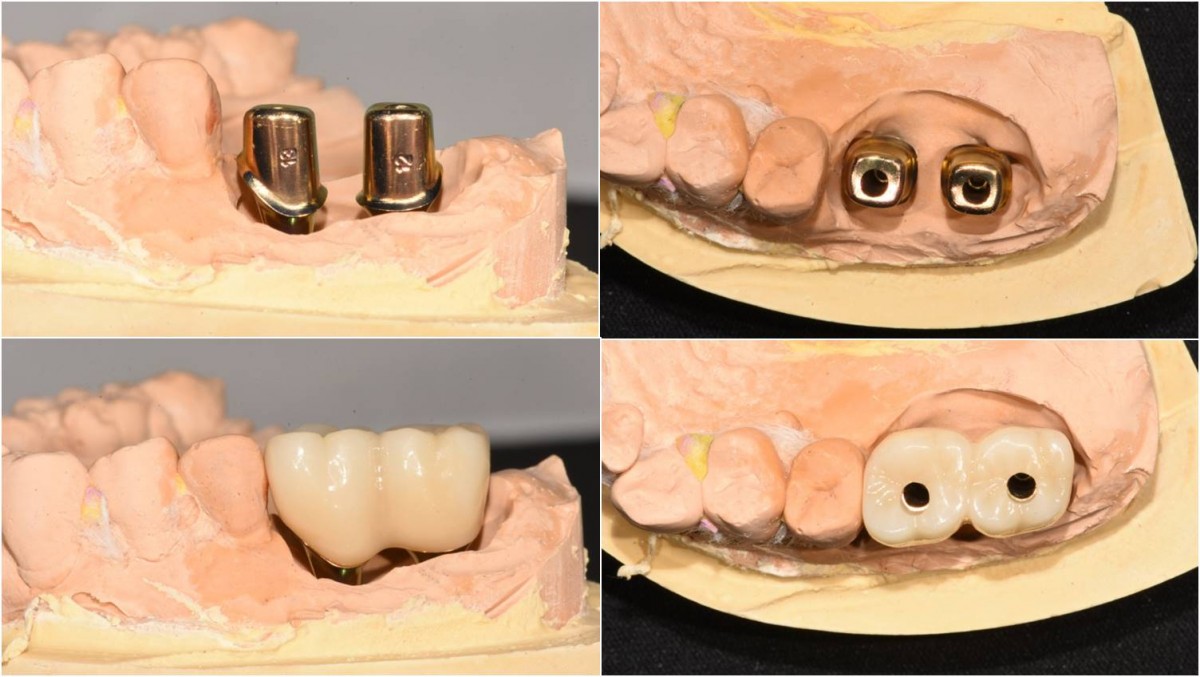

Maxillary Sinus Graft, 2 Implants, Crown Contouring